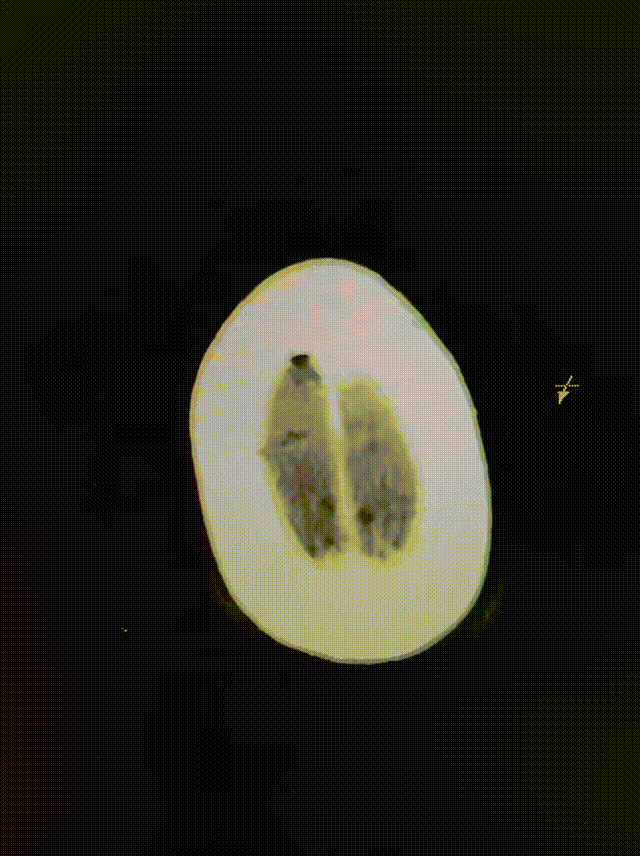

确认血栓完全取出后,球囊泄压,术后即刻造影显示大脑中动脉闭塞再通, mTICI评分3级。

动脉长鞘怎么置入健谈•一鞘双能|温昌明教授团队:BMAX088球囊长鞘治疗左侧大脑中动脉闭塞一例_https://www.jmylbn.com_新闻资讯_第12张

动脉长鞘怎么置入健谈•一鞘双能|温昌明教授团队:BMAX088球囊长鞘治疗左侧大脑中动脉闭塞一例_https://www.jmylbn.com_新闻资讯_第13张

无明显造影剂渗漏及脑梗死表现。